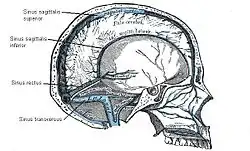

Der Sinus sagittalis superior verläuft in einer gedachten Mittellinie unter dem Schädeldach entlang der sogenannten Hirnsichel (Falx cerebri). Der Sinus sagittalis inferior verläuft im freien Rand der Falx über dem Balken und mündet zusammen mit der Vena cerebri magna in den Sinus rectus. Dieser verläuft gerade nach hinten zum Confluens sinuum, in den auch der von oben kommende Sinus sagittalis superior einmündet. Ebenfalls verbunden ist hier der Sinus occipitalis. Die paarigen Sinus transversi leiten das Blut vom Confluens weiter zur hinteren Schädelbasis, wobei sie sich im Verlauf S-förmig winden und ab dort als Sinus sigmoidei bezeichnet werden. Schließlich münden sie in die tiefen Halsvenen. Der Sinus cavernosus ist ein schwammartiges Netz, das auf dem Keilbein liegt und mit dem übrigen venösen Sinussystem durch jeweils einen Sinus petrosus superior und inferior auf jeder Seite verbunden ist.